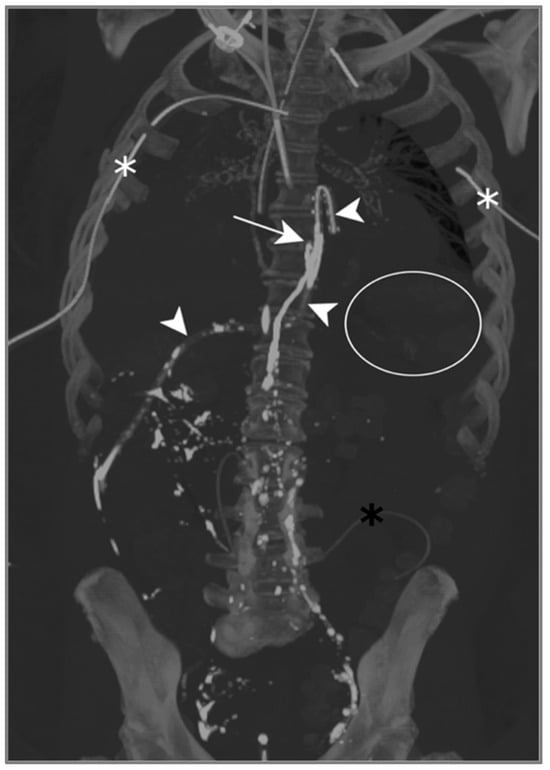

The contrast injected in the inguinal region showed ascension into the thoracic duct up to the level of the inferior vertebral plateau of D7, as well as the leakage and accumulation of Lipiodol in both pleural spaces: Lipiodol also accumulated in the drain coming into contact with the esophago-jejunal anastomosis (Figure 5).

Figure 5.

Patient A. The maximal-intensity projection of the CT scan reconstructed in the coronal plane. The Lipiodol injection shows opacification of the left inguinal and prevertebral lymphatic chains up to the level of the inferior vertebral plateau of D7 (white arrow). The drainage of the contrast agent through the catheter along the oesophagojejunal anastomosis is highlighted (white arrowheads). The subtle soft attenuation in the projection of the left lung field (white circle) corresponds to the accumulation of contrast in the pleural space due to the lymphatic rupture. The bilateral pleural catheter (white asterisks) and peritoneal drain (black asterisk) are identified.

One day after lymphangiography, the drain output had diminished by half, and reduced to less than 100 mL/d as of day 2. Per-mouth nutrition was begun progressively, with no recurrence of chylous effusion, allowing for drain removal on day 13.

Lymphangiography was therefore successful in treating this bilateral post-operative chylothorax.